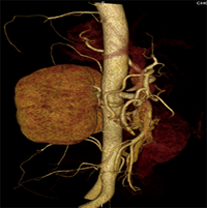

同一病人利用容積數(shù)據(jù)進(jìn)行三維處理后,高品質(zhì)MPR和三維圖像上則清晰顯示了縱向排列的腹腔干與腸系膜上動(dòng)脈相鄰近,血管發(fā)生變 異,近端血管閉塞,為臨床提供了精確的診斷信息。